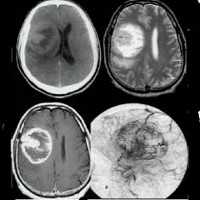

Наиболее приемлемым способом диагностики глиомы головного мозга на сегодняшний день является МРТ головного мозга. При невозможности ее проведения может применяться МСКТ или КТ головного мозга, контрастная ангиография мозговых сосудов, сцинтиграфия. ПЭТ головного мозга дает сведения о метаболических процессах, по которым можно судить о скорости роста и агрессивности опухоли. Кроме того, с диагностической целью возможно проведение люмбальной пункции. При глиоме головного мозга анализ полученной цереброспинальной жидкости выявляет наличие атипичных (опухолевых) клеток.

Диагноз опухоли зрительного нерва устанавливается на основании клинических данных, результатов исследования зрительной функции и глазного дна, данных рентгенологического исследования и компьютерной томографии.

Зачастую первым врачом, к которому обращаются пациенты с глиомой зрительного нерва является офтальмолог. Проводя проверку остроты зрения, он выявляет ее снижение, в ходе периметрии и компьютерной периметрии в поле зрения могут обнаруживаться отдельные скотомы. Осмотр глазного дна (офтальмоскопия) в ранних стадиях развития глиомы зрительного нерва может не выявить наличия каких-либо изменений. Позже определяется застойный диск зрительного нерва и картина, характерная для вторичной атрофии зрительного нерва. Может отмечаться тромбоз центральной вены сетчатки. В случаях, когда глиома зрительного нерва прорастает диск зрительного нерва, при офтальмоскопии определяется овальное или округлое образование желтовато-розовой или белой окраски, которое может иметь как бугристую, так и гладкую поверхность. При интракраниальной глиоме наблюдается первичная атрофия зрительного нерва.

Наиболее достоверно глиома зрительного нерва диагностируется при помощи КТ головного мозга, которое позволяет визуализировать утолщенный зрительный нерв, определить границы разрастания опухоли и ее прорастание в полость черепа. При невозможности проведения КТ, используют прицельную рентгенографию черепа и рентгенографию орбиты, которые при интраорбитальной локализации глиомы выявляют одностороннее расширение полости орбиты и канала зрительного нерва, их затемнение, истончение стенок глазницы.